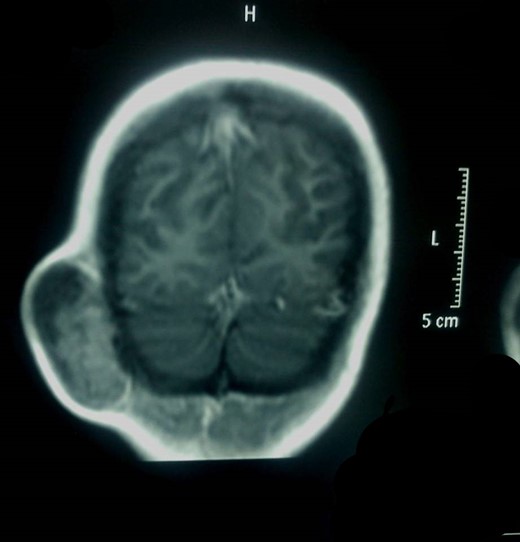

Α 12-year-old girl presented to us with a painless tumefaction on the right suboccipital region evolving for 5 months. Clinical examination did not reveal any other important symptoms or signs. Various explorations carried out, in particular, X-rays (Fig. 1), CT scan with intravenous contrast medium (Figs 2 and 3) and imagery by magnetic resonance with intravenous paramagnetic contrast.

MRI showed an encapsulated spindle formation in the region of the soft tissues of the right suboccipital region (Fig. 4). It was primarily located in the subcutaneous tissues, with a broad attachment to the outer table of the diploe, which appears to be thinned. It had mainly intermediate signal on T1W and T2W images, combined with some areas of high signal on T2 and low signal on T1. After the intravenous injection of the contrast, it showed inhomogeneous uptake.